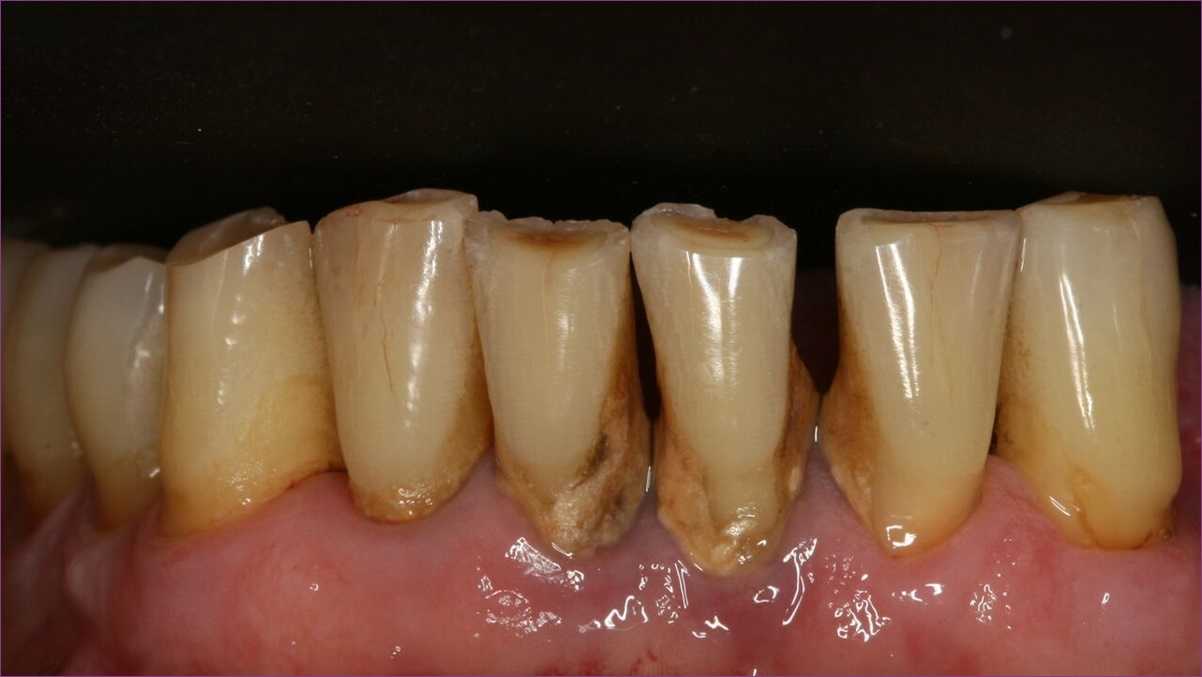

A fogkő eltávolítása nagyon fontos, mivel a fogkő okolható a fogszuvasodások zöméért, és az ínygyulladásnak is fő kiváltó oka. Továbbá a kellemetlen lehelet forrása, és – mint a képen is látható – látványnak sem vonzó.

A depurálás során, azaz a fogkő eltávolításakor ultrahangos depulátorral leszedjük a fogkő íny alatti és íny feletti részét. Ezután következik a polírozás, hogy a maradék lerakódásoktól és a fogak elszíneződését okozó anyagoktól is megszabadítsuk a fogakat. Ilyenkor a fogak minden felületét végigpolírozzuk a különböző polírozó eszközökkel.

Részleges fogtisztításra akkor kerül sor, ha a professzionális fogtisztítást egy ülésben nem lehet elvégezni. Ez főként olyankor fordulhat elő, amikor a fogkő mennyisége és kiterjedése igen jelentős.

Az okok között szerepelhet az is, hogy a páciens ínye annyira be van gyulladva (többnyire éppen a nagy kiterjedésű fogkő miatt), hogy a szakorvos nem tudja a teljes fogtisztítást elvégezni az érzékeny és vérzékeny íny miatt.